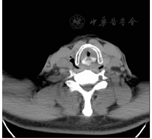

患者,男,51岁,1 d前无明显诱因出现右上腹疼痛不适,伴有发热,无畏寒,无胸闷、心悸,无恶心、呕吐,无头痛、头晕,无腹泻、黑便,无尿频、尿急、尿痛等症状,遂就诊于当地医院,查腹部B超示胆囊结石、胆囊炎。为求进一步治疗来院就诊,门诊拟"胆囊结石伴急性胆囊炎"收入病房。患者自发病以来,精神、饮食、睡眠欠佳,有声音嘶哑,有呼吸急促史,大小便正常,体质量较前无明显变化。患者既往有胸部外伤史,具体不详;否认糖尿病、高血压病史,否认肝炎、结核病史,否认输血史,否认食物、药物过敏史。诊断为胆囊结石伴急性胆囊炎,术前血气分析为低氧状态,拟于2016年6月20日在全身麻醉下行腹腔镜下胆囊切除术,麻醉师诱导后在直接喉镜下无法插入4.0号气管插管,并发现声门区肿胀,声门下区严重狭窄,黏膜易出血;给予喉罩下吸氧,患者二氧化碳分压>60 mmHg(1 mmHg=0.133 kPa)。请耳鼻咽喉科急诊下行气管切开,切口2、3气管软骨后见气管严重狭窄并有肿瘤样组织,取部分肿瘤样组织送病理检查,并强行入4.0号气管插管,改善患者通气,但患者的二氧化碳分压较大,给予扩大切口并放入6.0号气管插管,术后转重症监护病房。转重症监护病房后行颈胸部CT检查示:喉黏膜增厚,气管、右支气管内见环形高密度钙化影,上段气管见明显狭窄(见封四图1、图2),双侧肺不张。次日上午再次出现呼吸困难,发热,脉搏氧饱和度(SpO2)下降,立即给予甲泼尼龙静脉推注,利多卡因气道内滴入,氨茶碱泵入,并给予呼吸兴奋剂泵入,患者氧合情况逐渐好转,血氧饱和度最高达91%,于12∶00出现血压下降,立即予去甲肾上腺素0.11 μg/(kg·min)泵入,同时给予静脉补液,经治疗后生命体征不平稳,查体:体温(T)37 ℃,心率(P)72次/min,呼吸(R)27次/min,血压(BP)88/50 mmHg,血氧饱和度(SpO2)88%,气管导管在位,重度昏迷状态,患者家属放弃治疗,出院后不久死亡。术后病理示:黏膜下结缔组织增生伴淀粉样变性(见封四图3)。

LTBA在内窥镜下呈喉及气管内弥漫性肿胀,偶见黏膜下结节状团坎,不伴溃疡,常呈黄色、半透明石蜡状。LTBA影像学诊断主要靠CT。因CT能够显示病灶内部结构,喉气管支气管粉样变性由于蛋白质沉着可出现不同程度钙化,CT同时可分辨钙化与成骨性钙化不同,并且CT通过调动窗宽窗位可以清楚显示钙化,也是与喉部恶性肿瘤的鉴别之一。淀粉样变部位CT密度较高,一般高于肌肉密度,CT值40~60 Hu,可以帮助诊断,但在病变周围常伴有局部的慢性炎性反应。由于淀粉样物质呈块状、斑片状沉积在黏膜下,故CT上表现为增厚的室带等喉腔内组织、气道管壁增厚,气管黏膜面多凹凸不平,呈结节状、波浪状,管腔不规则狭窄。CT可清楚地了解气道内淀粉样变性为局限性还是弥漫性:局限性表现为管壁的局限性结节,管腔向心性狭窄;而弥漫性则为管壁的弥漫性围管性增厚。同时,CT三维重建还有助于了解病变范围并制订详细的手术方案。而常规喉部X线侧位片和正位片仅能提示喉部有病变,只对喉部淀粉样变性具有一定诊断价值[5]。